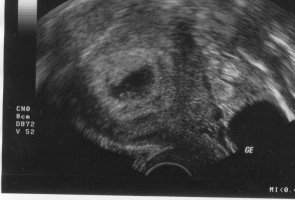

es ist amtlich :banane:.

Herzchen bubbert fleißig und alle Werte sind Top. Mein ET hat sich auf den 11.11.09 vorgeschoben

• 7. woche.jpg

Obwohl man noch nicht so wirklich viel erkennen kann, macht allein das Bild eine Gänsehaut bei mir, weil ich mich so sehr mit-freue :zwinker: